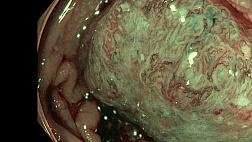

Необходимость поиска эффективных средств лечения ГЭРБ особенно велика при эрозивных ее формах, доля которых среди всех случаев данного заболевания составляет более трети. Учитывая большой риск развития аденокарциномы, появления стриктур пищевода при язвенных поражениях, сокращение времени использования препаратов ИПП представляется особенно актуальным.

В выступлении «Эффективное заживление эрозий и язв: формула успеха терапии», оценивая эффективность лечения больных с язвенной формой ГЭРБ, главный гастроэнтеролог Москвы Д.С.Бордин , д.м.н. главный гастроэнтеролог г. Москвы, указал на существенные различия в сроках терапии с использованием омепразола и декслансопразола с модифицированным высвобождением. В соответствии с принятым протоколом лечения ИПП рекомендуется использовать в течение 8 недель. Однако, прием Дексиланта дает успешные результаты уже после 4 недель – 80%, а после 8-ми – достигается 93% эффективность.